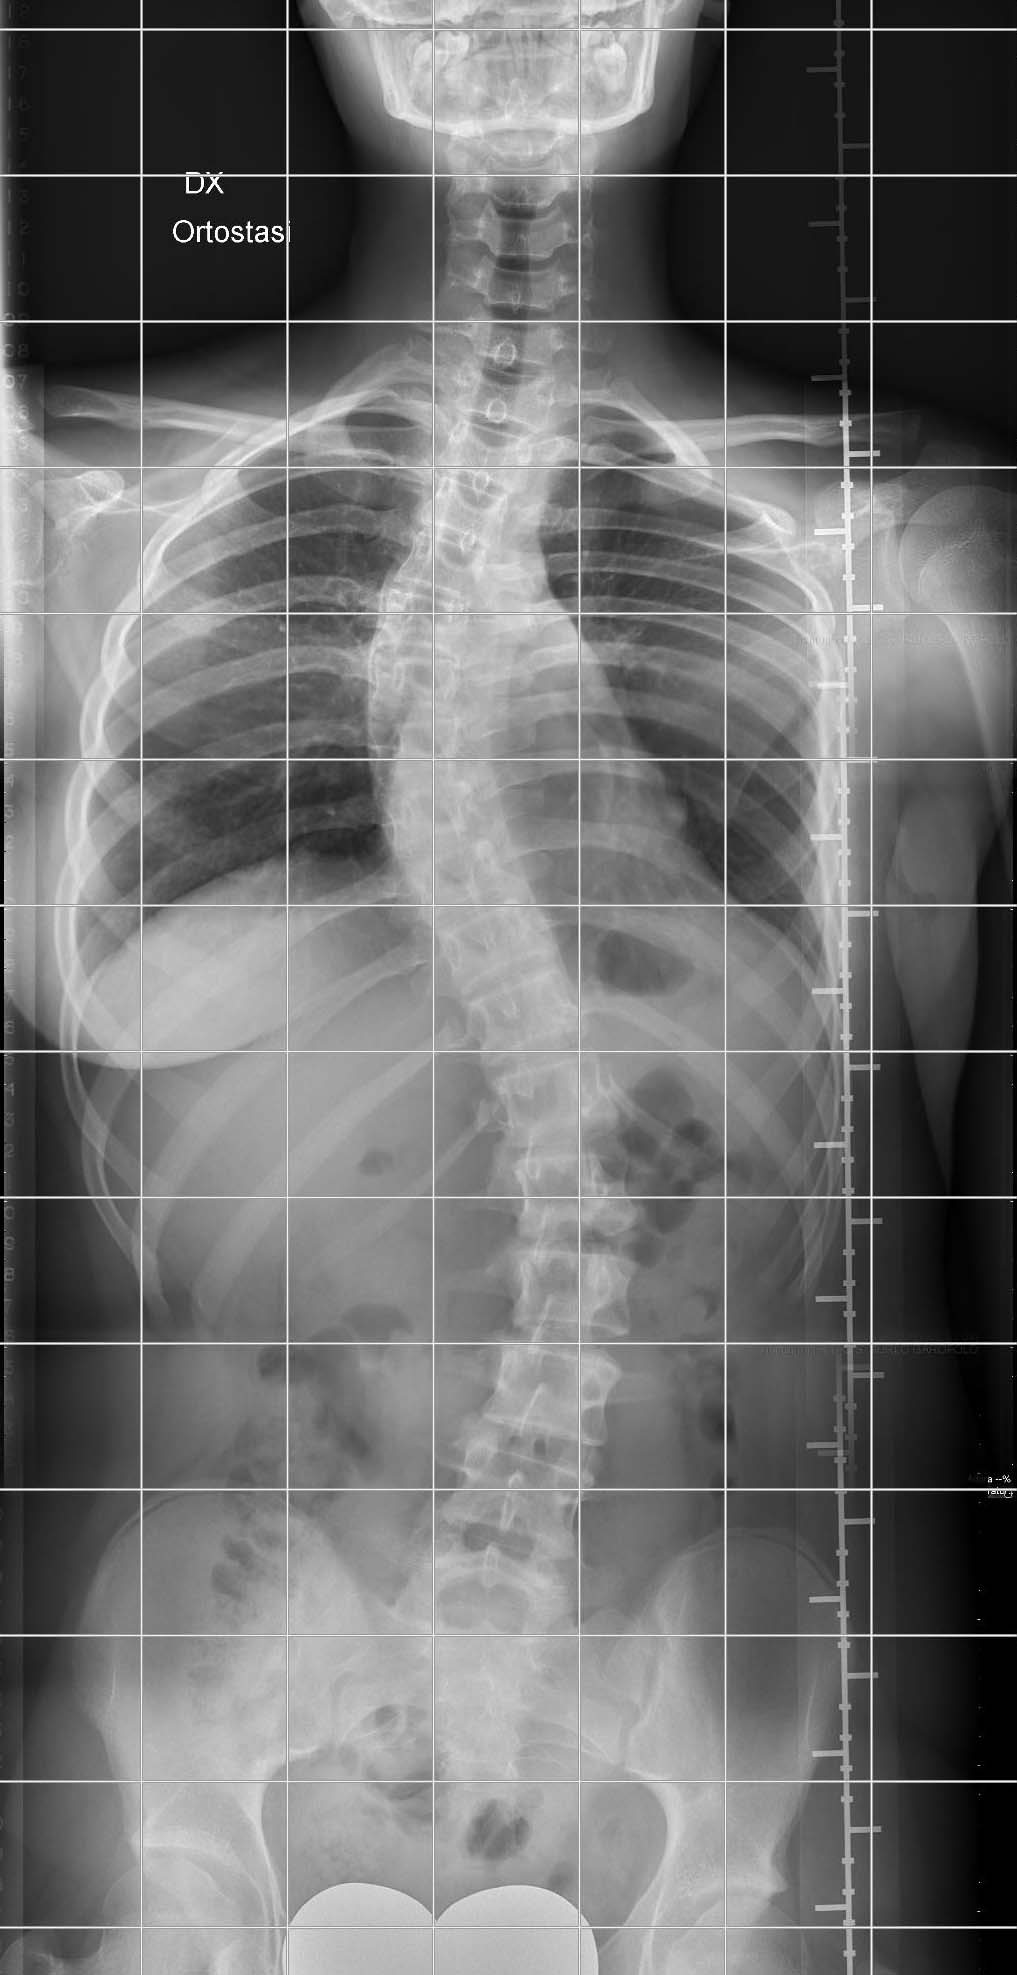

In proiezione postero-anteriore, va effettuata a soggetto in piedi con le gonadi protette. È raccomandata l’esecuzione presso una radiologia con disponibilità di apparecchiature dedicate.

L’utilità di una radiografia in proiezione laterale è oggetto di discussione: raccomandata in molte linee guida nella prima valutazione o in caso di evidenza clinica di una alterazione del profilo del rachide sul piano sagittale, come il dorso piatto, o di dolore, negli altri casi probabilmente non aggiunge informazioni utili.